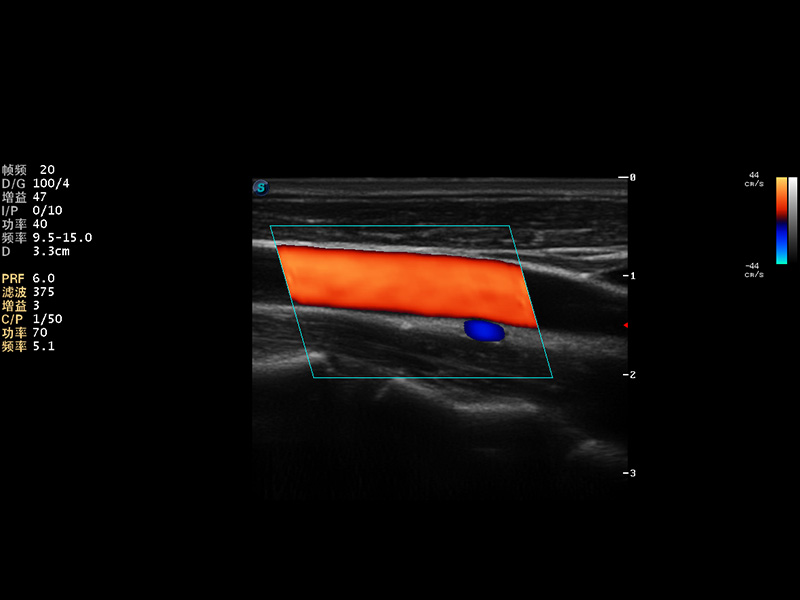

S9便携式彩色多普勒超声诊断仪是狗万官方网站研发的高端便携彩超设备,外观设计新颖、产品性能卓越。S9在便携超声领域采用了突破传统的触摸屏交互设计,并以先进的软件硬件技术和设计理念,为您带来清晰的图像质量、稳定的工作性能和便捷的操作体验。

VIS平台设计

μ-Scan微米成像

AutoC智能血流追踪